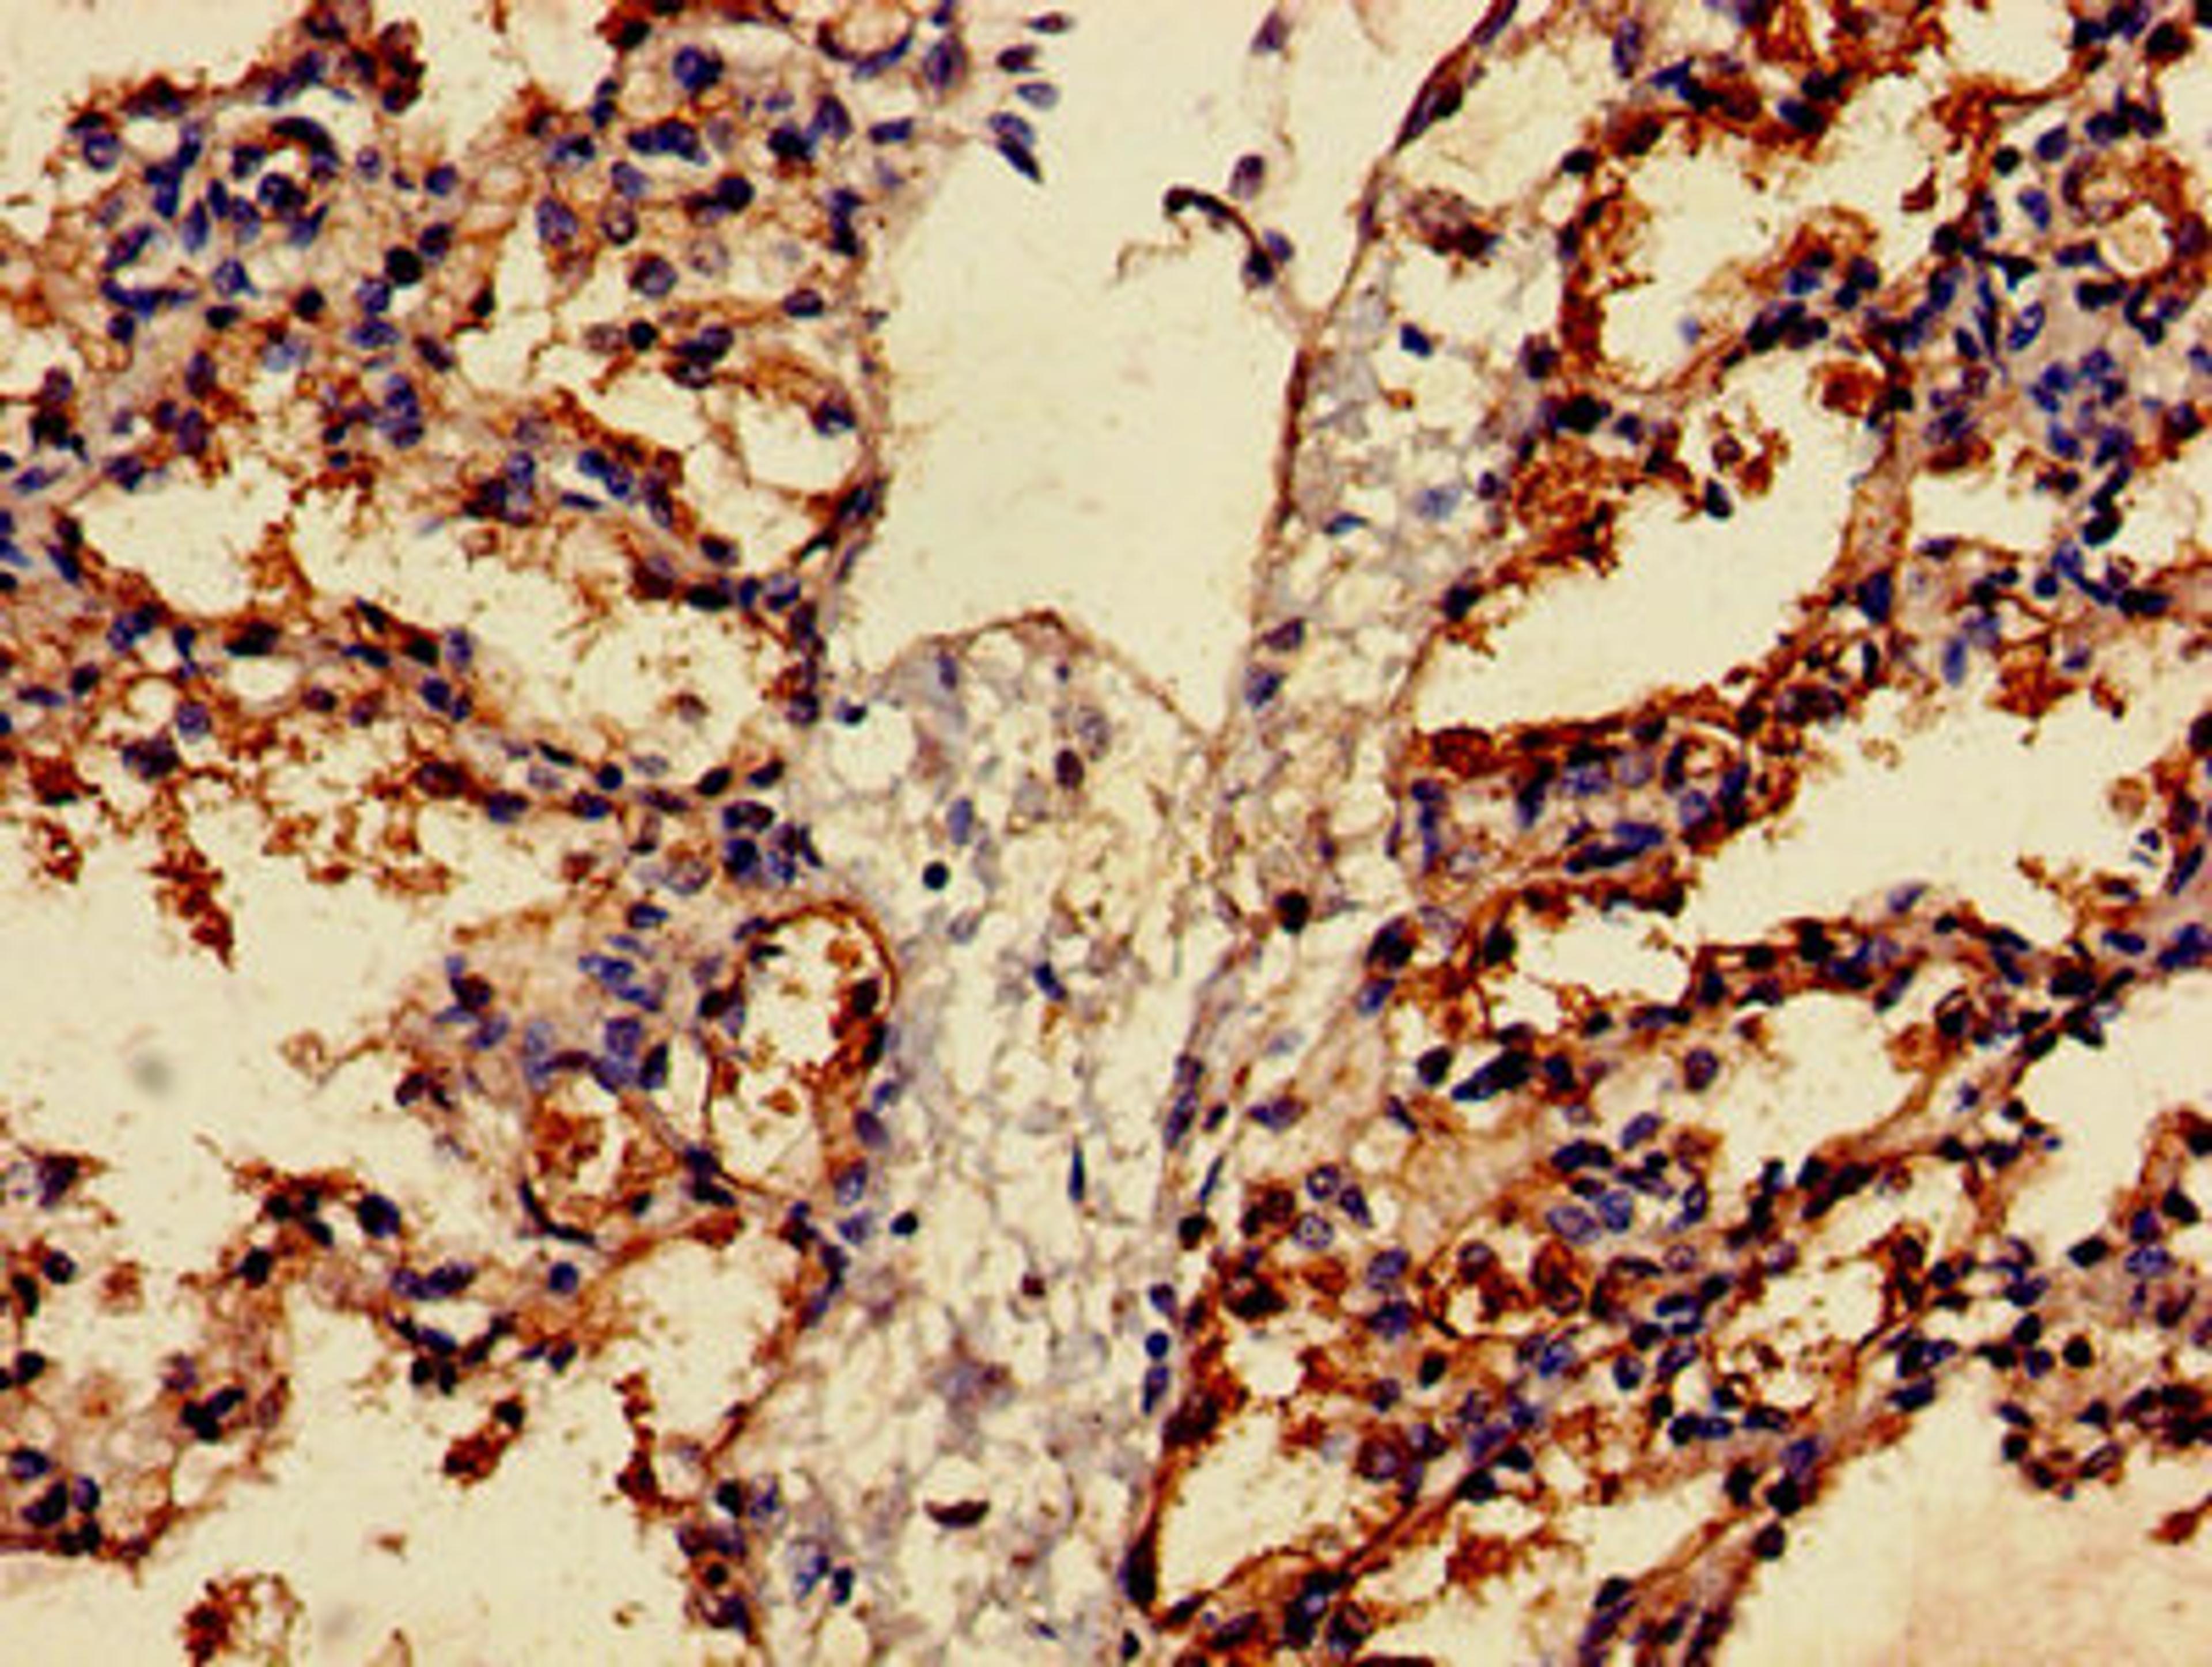

- Immunohistochemistry (IHC)